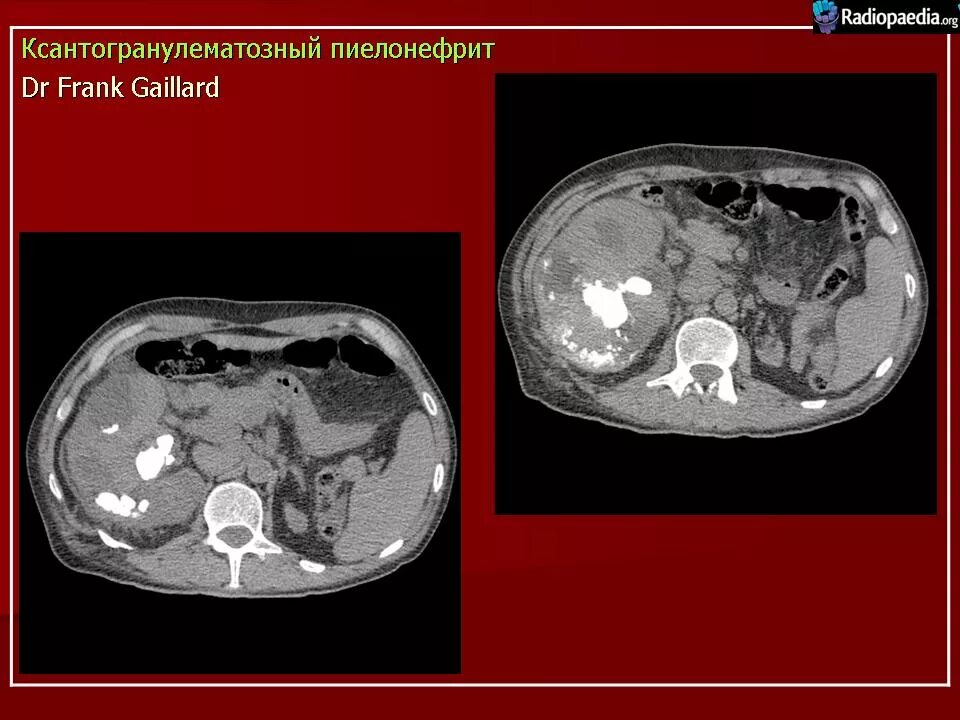

Пиелонефрит кт